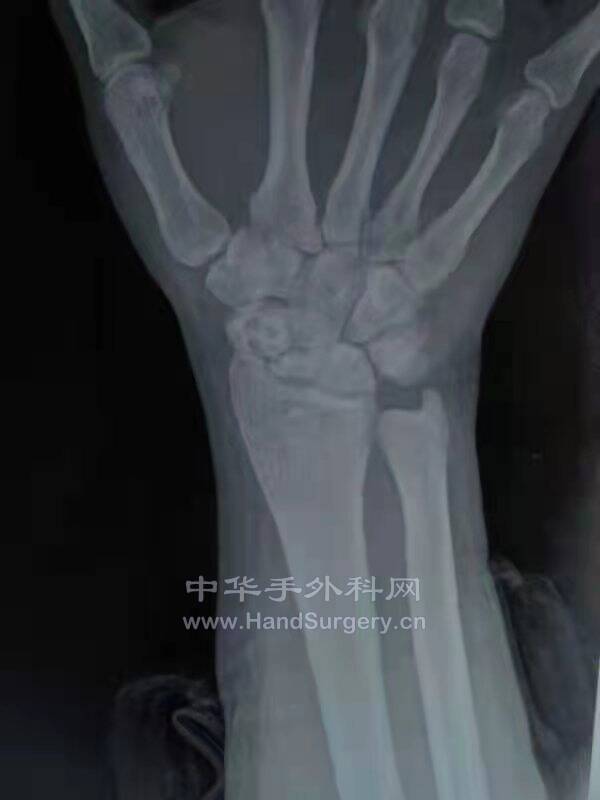

舟月进行性塌陷SLAC

舟骨不愈合进行性塌陷SNAC

临床上,我们可以把舟骨不愈合造成的关节炎的发展过程分为四期。

Ⅰ期特点是桡骨茎突处关节炎表现,骨赘形成;

Ⅱ期表现是桡舟关节骨性关节炎;

Ⅲ期,关节炎累及舟头和头月关节;

Ⅳ期为全腕关节炎(桡月关节除外)。

这一发展过程称为“舟骨不愈合进行性塌陷”,即SNAC腕。